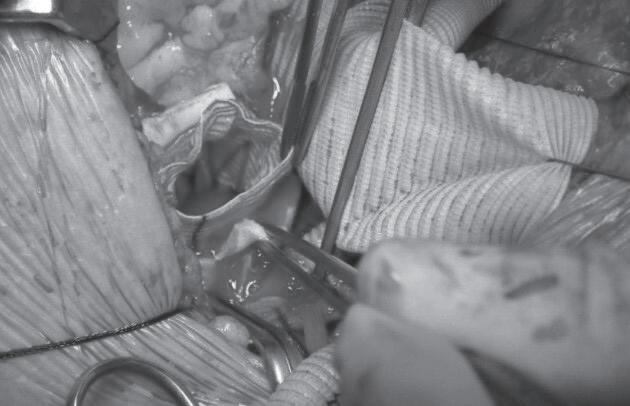

Na técnica de remodelamento de Yacoub (Fi gura 7.4), a aorta ascendente e os seios são subs tituídos por uma prótese tubular de interposição de dácron, que é fendido (“escalopado”) para incor porar os pilares comissurais da válvula aórtica.35 Os óstios coronários são então reimplantados. Como

FIGURA 7.2 (A a C) Esquema cirúrgico para o tratamento de aorta ascendente com preservação da válvula aórtica (A). Preservação da válvula aórtica e preparo do coto proximal (B). Interposição de tubo reto no segmento da aorta ascendente acima da junção sinotu bular até o início do tronco braquiocefálico (C) B C FIGURA 7.3 (A e B) Imagens demonstrativas da aplicação da técnica de David A B